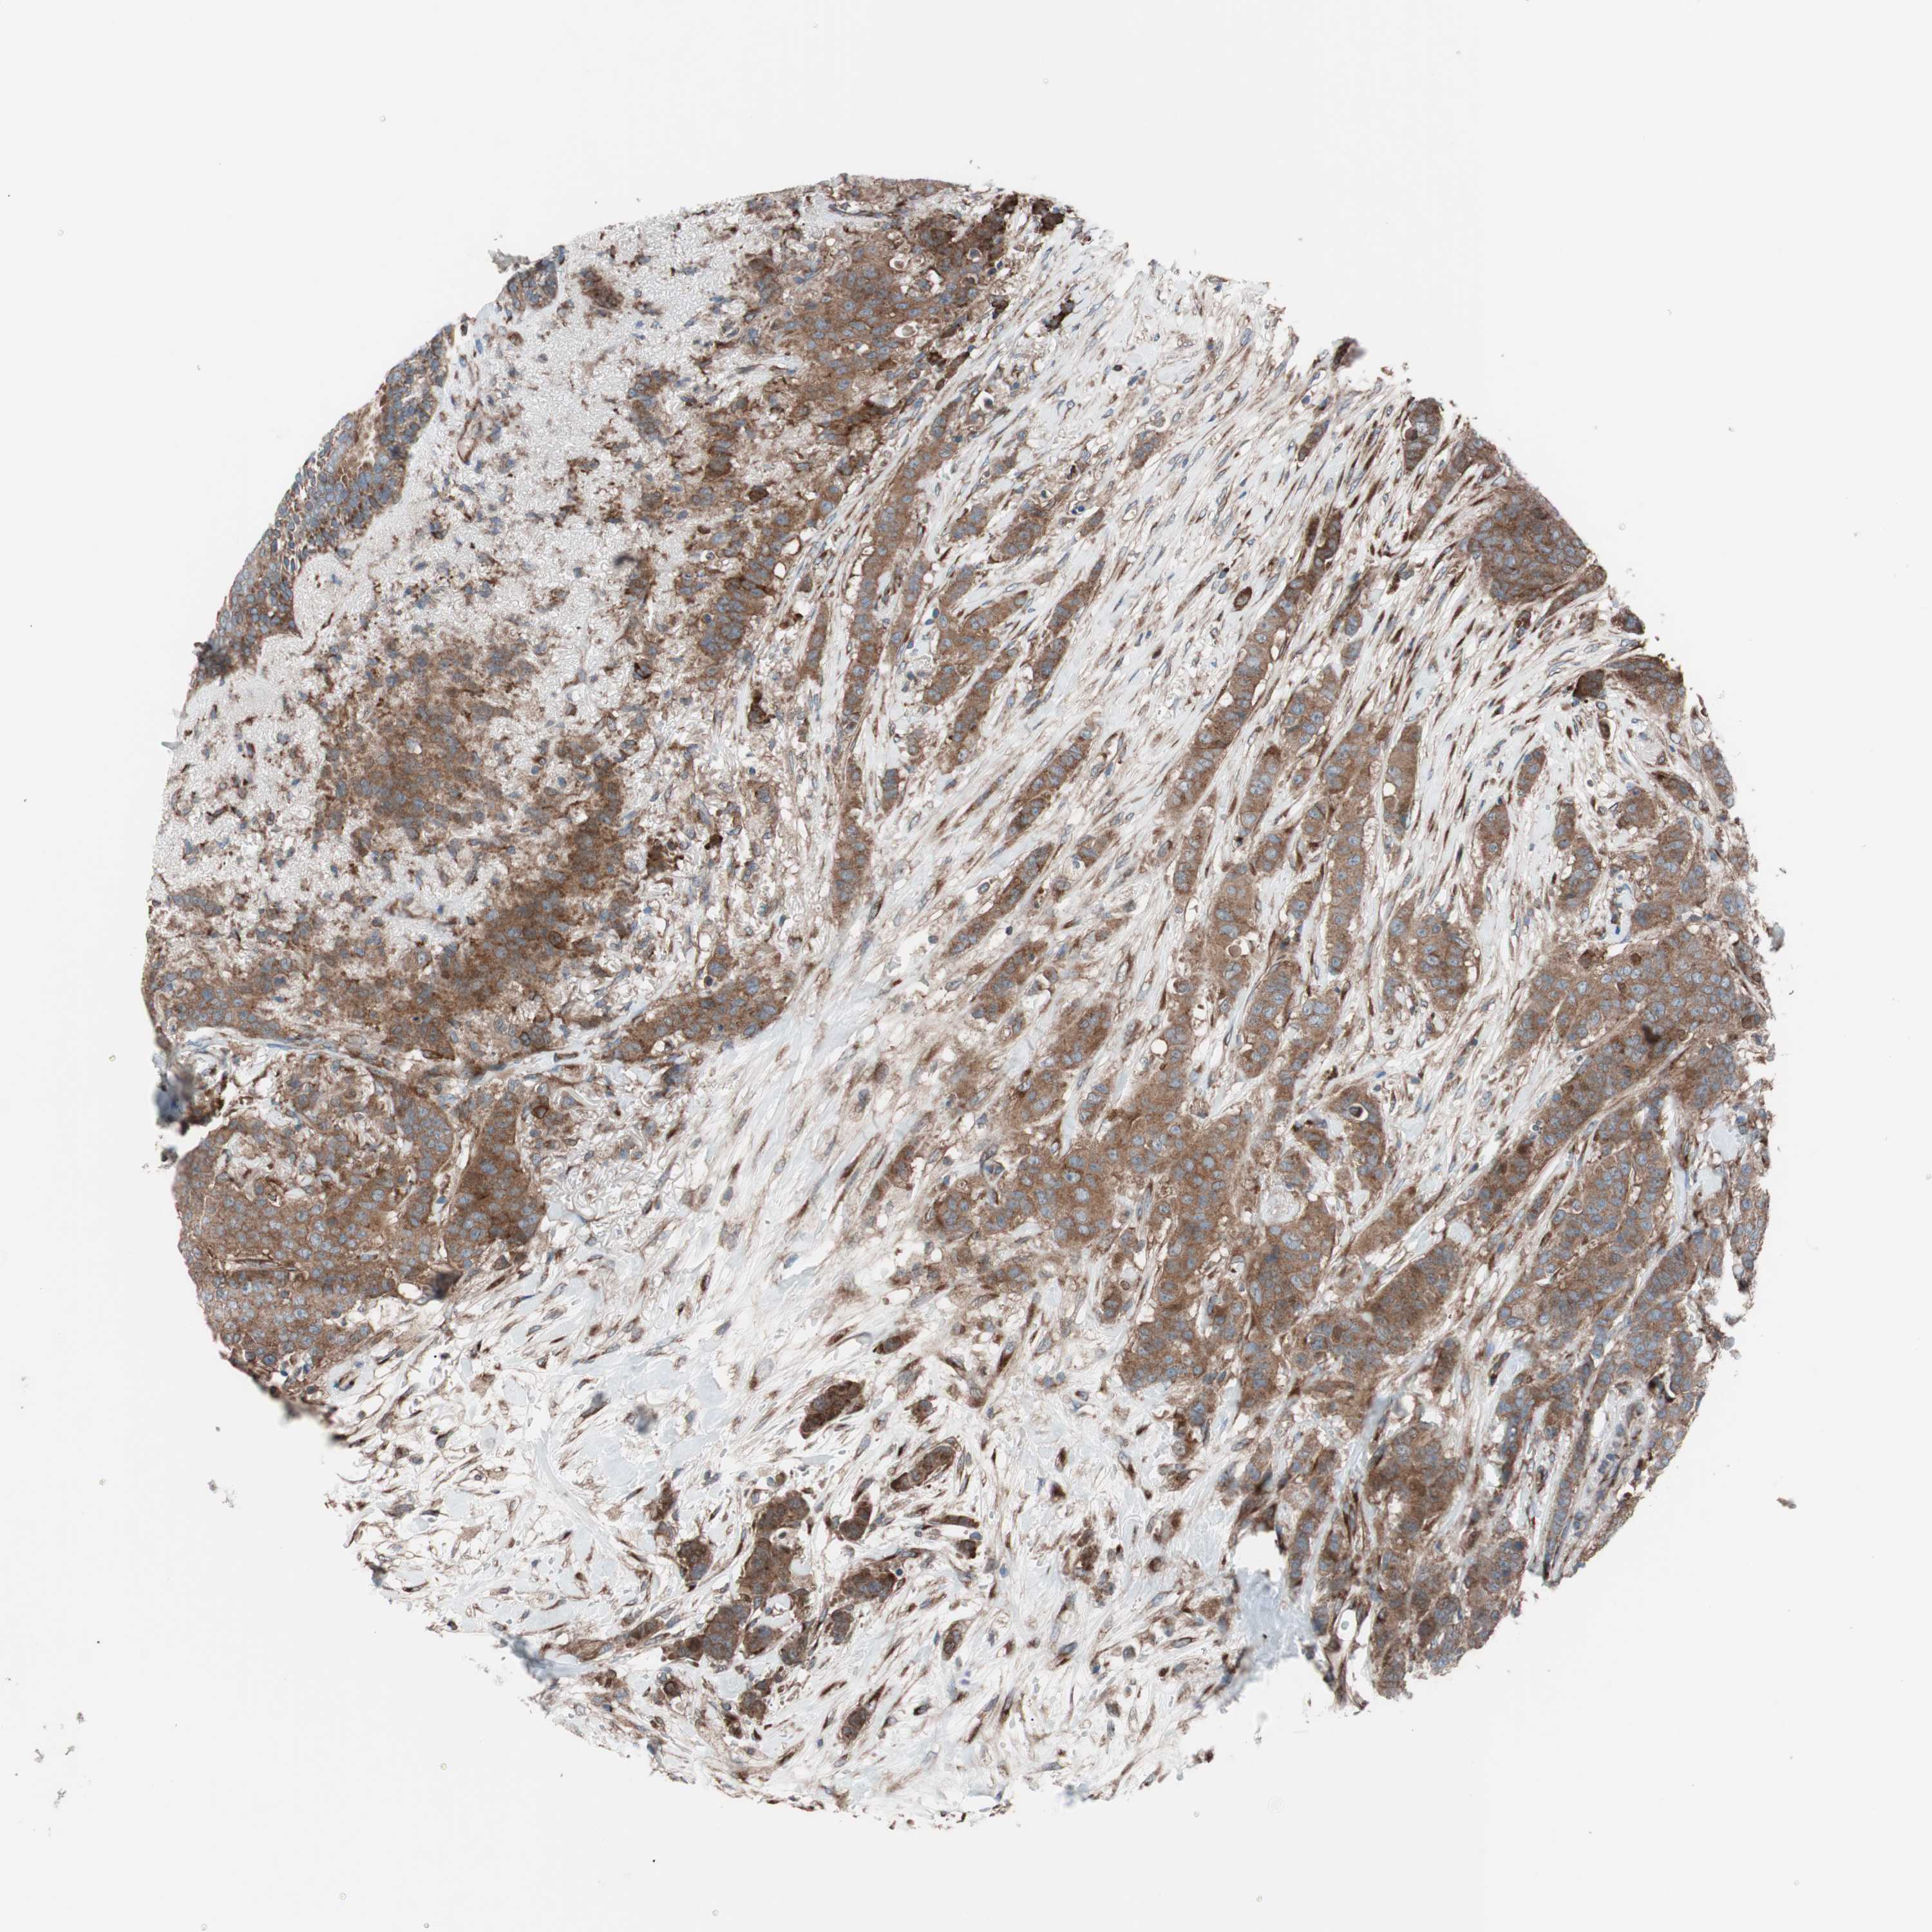

CANCER BREAST CANCER Show tissue menu

BRCA TCGA BRCA VALIDATION PROTEIN EXPRESSION